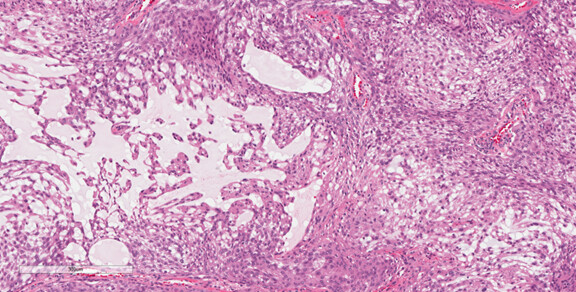

Representative Histology / IHC: